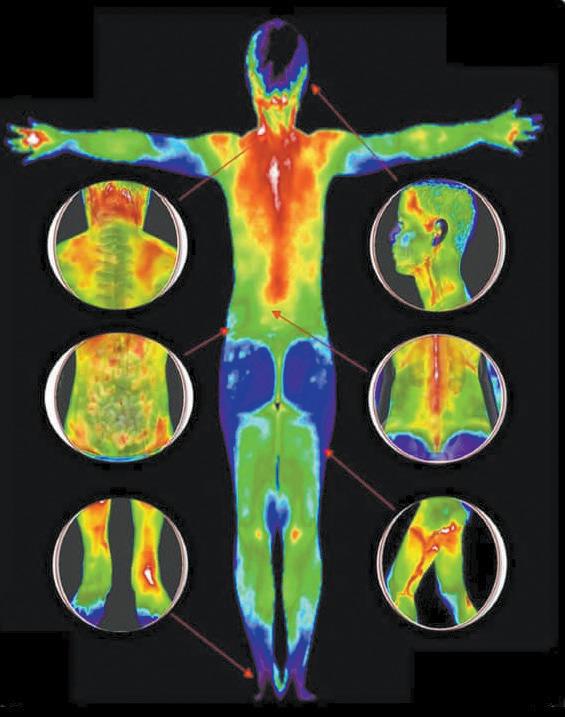

Positive Outcomes in Natural Healing for Complex Spine Conditions

Daniel Bishop, DPT, founder of Complex Spine Therapy in Daphne, is no stranger to chronic pain. After a traumatic car accident in high school led to a five-level spinal fusion and 18 months of rehabilitation, he experienced firsthand the challenges and triumphs of healing. That life-altering experience shaped his future—and his life’s work.

Today, Dr. Bishop brings more than 23 years of expertise in spinal health to his patients. A sixth-generation Baldwin County native, he has treated over 20,000 cases of serious spinal injury in the region and is known for his compassionate, tenacious approach to care. “I take every patient’s outcome personally,” he says. “Most people don’t realize that their spine can heal. It just needs the right conditions.”

body is capable of healing—even regenerating—when we support it properly.”

Combining advanced physical therapy with advanced dry needling, high intensity light therapy, shockwave therapy, PEMF, Advanced Postural Biomechanical Correction (APBC), postural alignment and individualized nutrition and lifestyle coaching, Bishop and his team help patients reduce pain and regain mobility. In many cases, complete resolution of symptoms—even with those with severe disc issues— happens in just a few weeks. He states, “I've had remarkable results with this problem for over 20 years in a market that is failing miserably at longterm solving this problem.”

in sequestered or extruded discs, is a documented phenomenon. With a comprehensive, conservative care plan, patients can often avoid surgery entirely.

Bishop is seeing remarkable outcomes in patients who were told they needed surgery, injections or lifelong medication. His clinic specializes in natural, non-surgical care for complex spine disorders, particularly degenerative disc disease and lumbar disc herniations—conditions often believed to be irreversible. “We’ve been led to believe that once the spine starts to degenerate, there’s no going back,” he explains. “But the

“Degenerative disc disease is often caused by poor posture, inactivity and strain from modern lifestyles,” he says. “This leads to inflammation, loss of disc height, and eventually nerve compression and spinal stenosis. But these tissues—especially the posterior disc, made of Type I collagen— are capable of healing with proper blood flow, nutrition and movement.”

Research confirms that spontaneous healing of spinal disc herniations, particularly

“We’re seeing near 100 percent success stopping pain almost immediately—without medication or surgery—using a powerful blend of advanced dry needling, high intensity light therapy, shockwave therapy, PEMF, Advanced Postural Biomechanical Correction (APBC) and lifestyle modifications.” -Dr. Daniel Bishop

Bishop is concerned about the growing trend of unnecessary spine surgeries and overuse of medications like opioids and steroids. “People in pain are vulnerable,” he says. “They’re desperate for relief, and too often they’re not told that there are other options. Conservative regenerative care should always be the first step.”

His approach reflects a deep belief in the body’s ability to heal—and in the importance of educating patients. “Only you can heal your disc problem with education and regenerative healing efforts to regenerate your disc back to normal,” he says. “But you don’t have to do it alone. With the right support, healing is not only possible—it’s expected.”